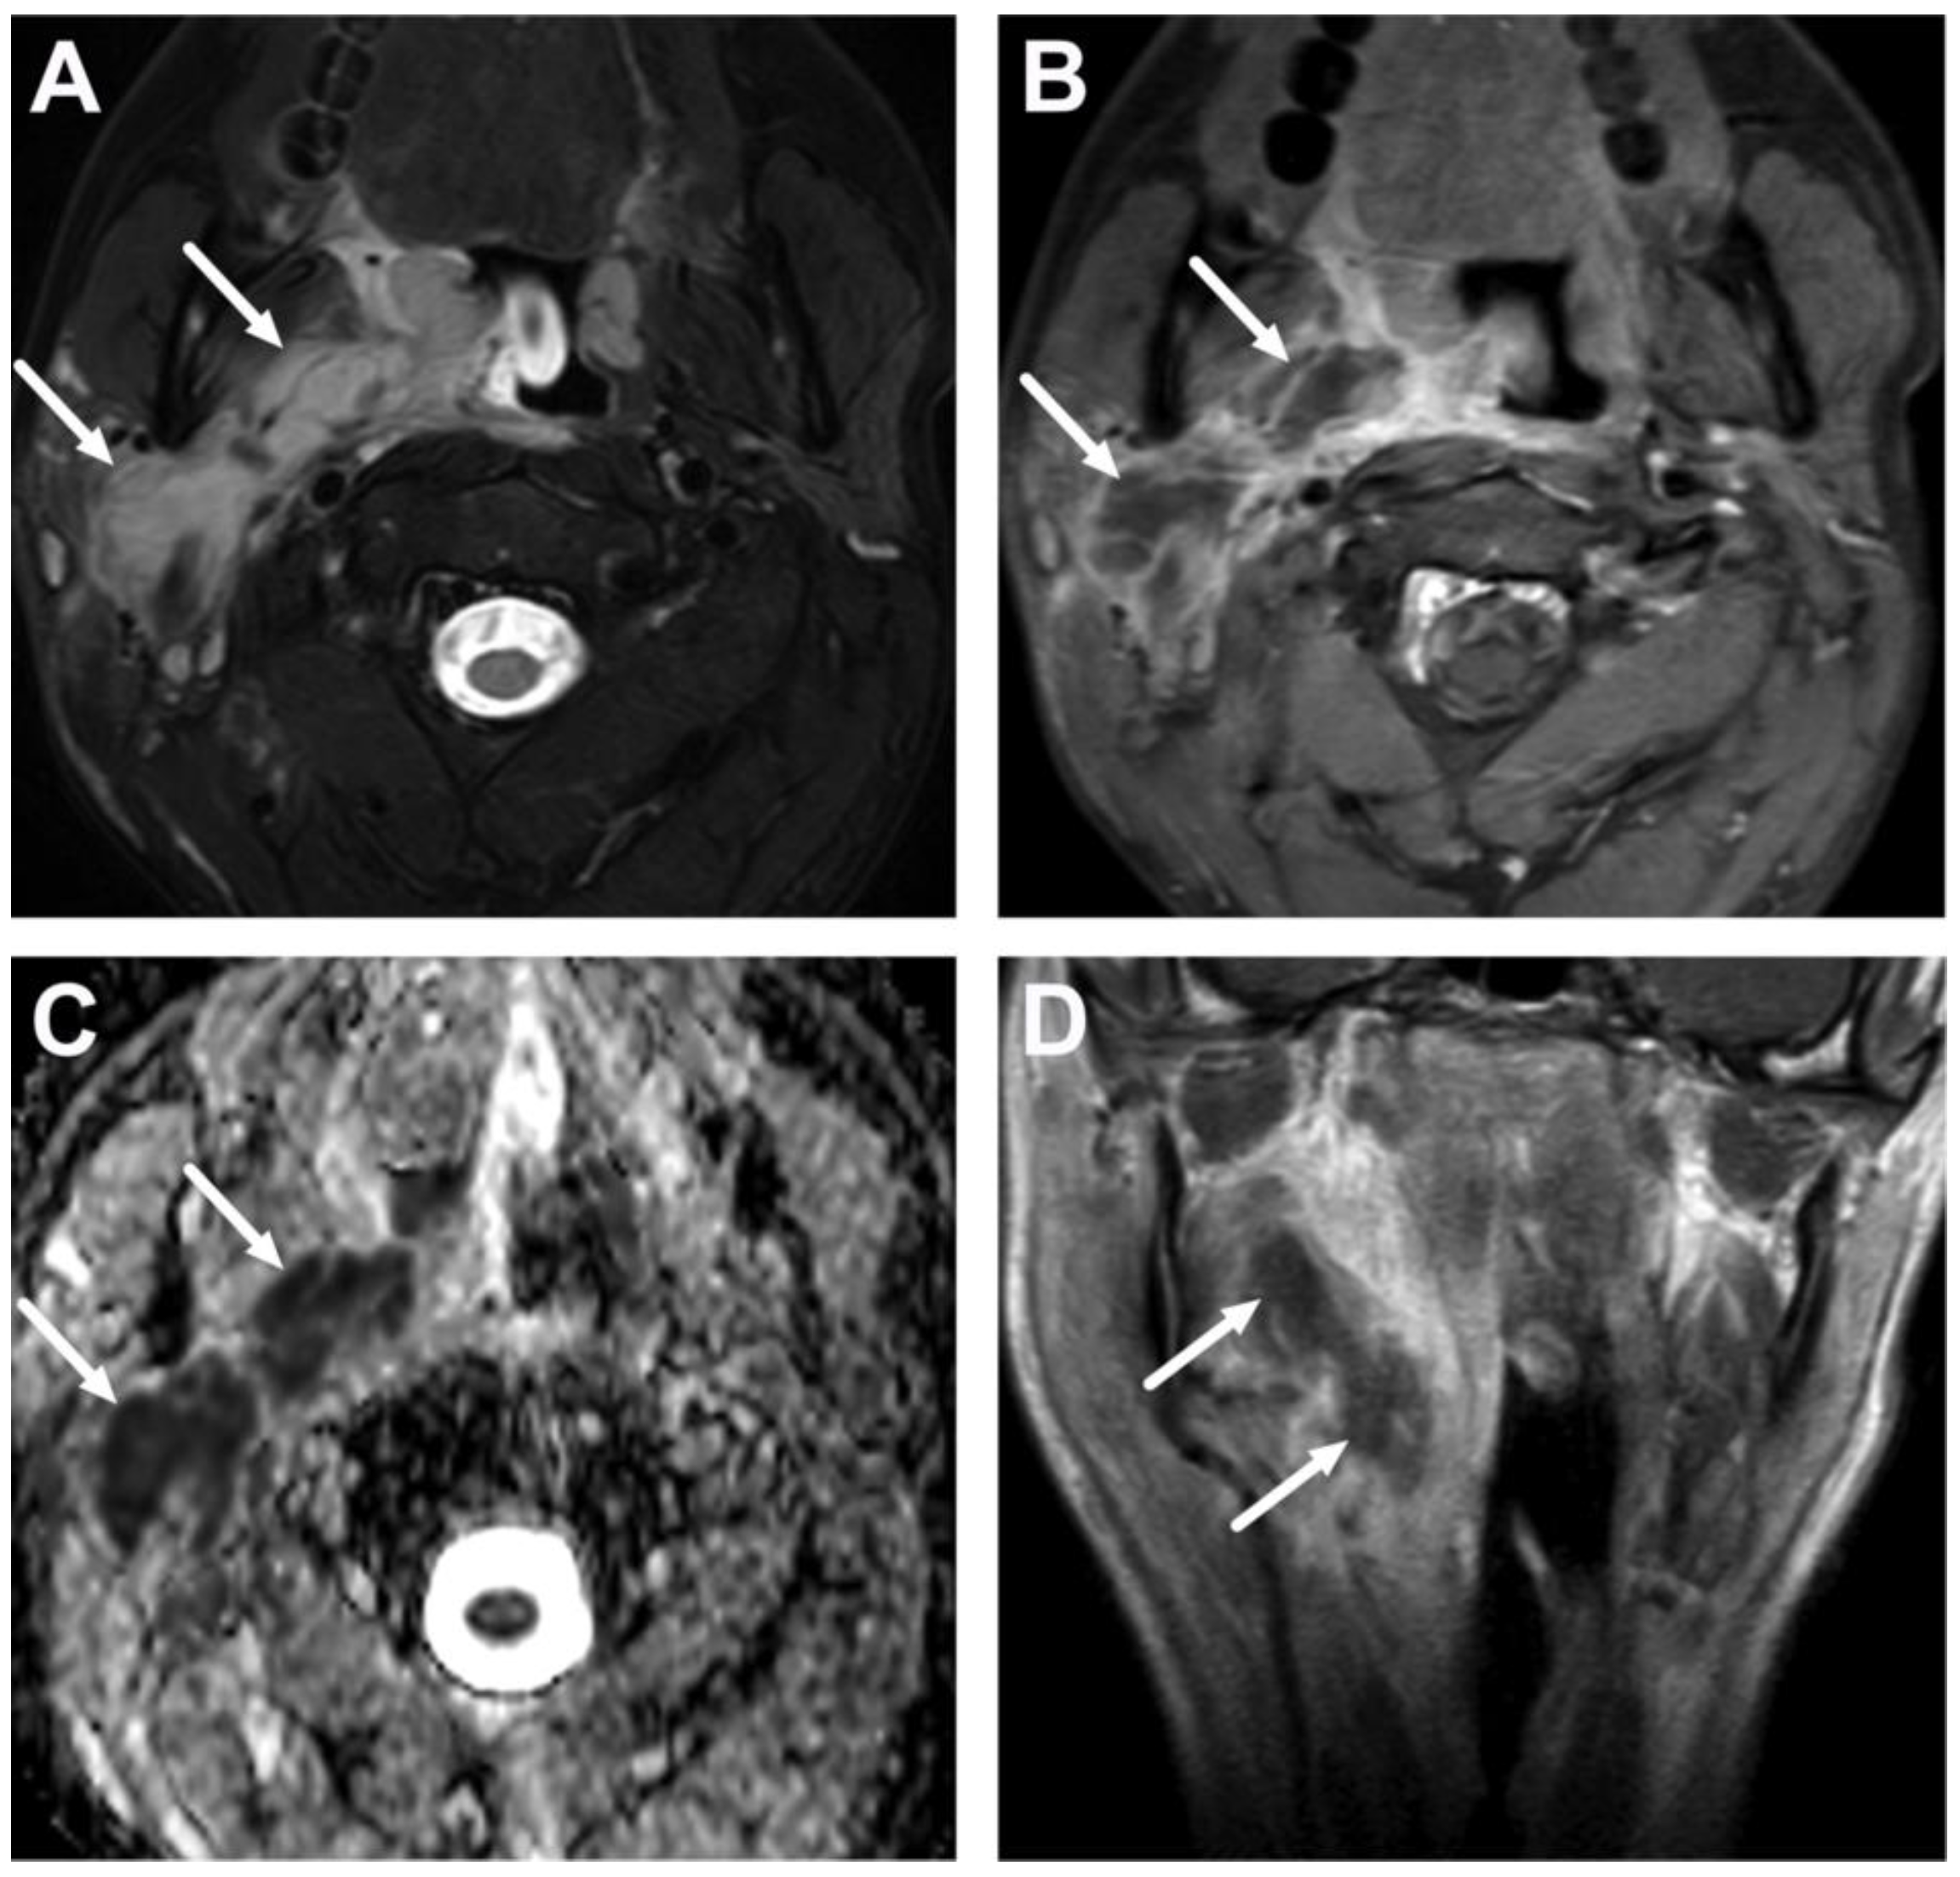

6.2. Venous Thrombosis

3.2. Terminology of Pathology

| Complications | Whole protocol | Abscess extending to multiple deep neck spaces, mediastinis, venous thrombosis, and airway compromise. | Detection of potentially life-threatening conditions. | Magnetic resonance angiography (MRA) or CECT may be needed to diagnose venous thrombosis; defining airway compromise is difficult. |